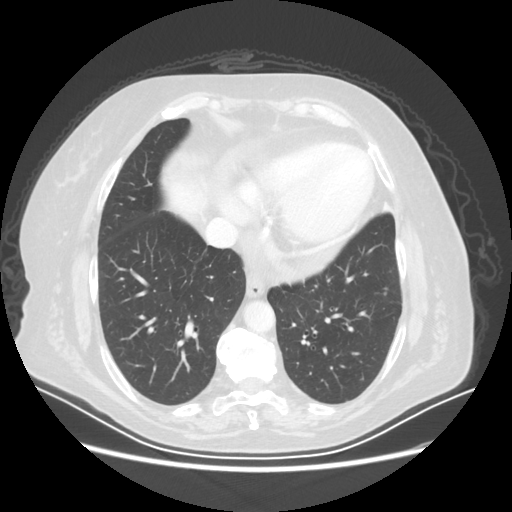

Original VENOUS CT scan

Lung window (WL -600, WW 1500 β†’ Low βˆ’1350, High +150)